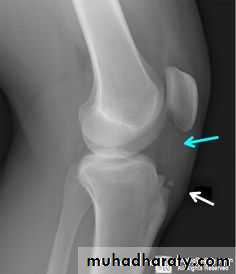

Osteochondritis dissecans of the medial femoral condyle

Osteochondritis dissecans of the medial part of the articularsurface

Osteochondritis dissecans :

affects the large articular surface , commomnly medial femural condylee ,talus and trochlea .

Ends by separation of the affected part in to the joint space resulting in intra-articular loose body .